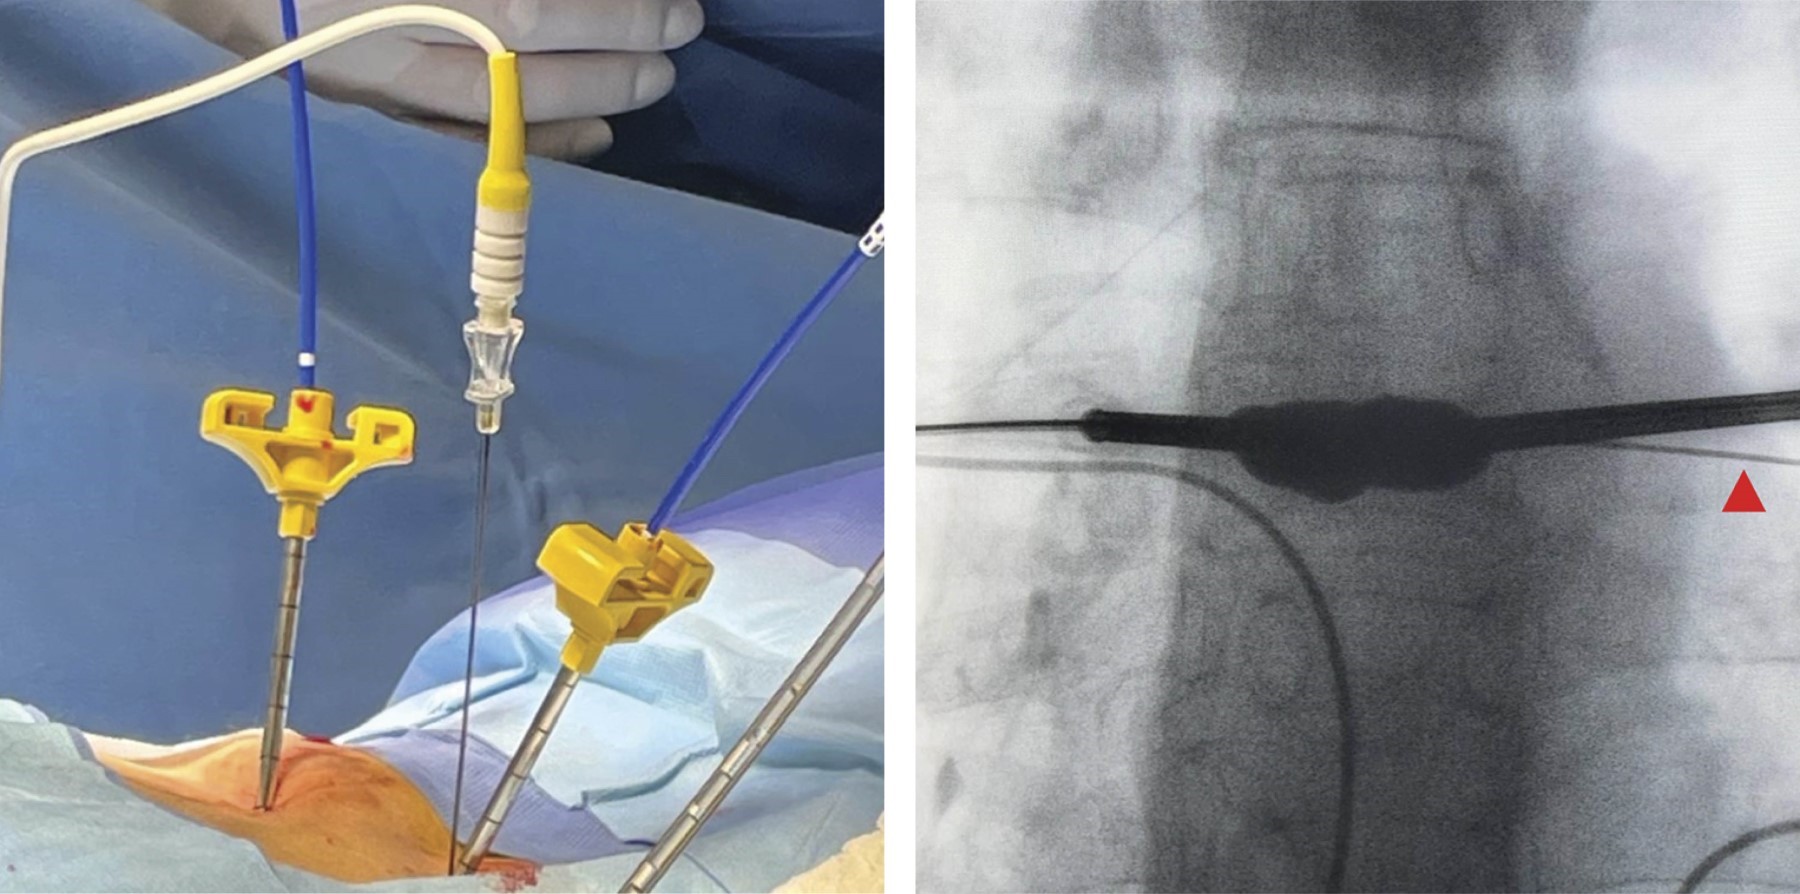

El procedimiento quirúrgico se estandarizó para todos los participantes. La cifoplastía se realizó con el paciente bajo anestesia general o sedación profunda según el criterio anestésico individualizado. La técnica implicó la inserción percutánea de cánulas a través de abordaje posterior bilateral hasta alcanzar la vértebra afectada, seguida de inflado de balones específicos para la restauración de la altura vertebral y estabilización del cuerpo vertebral con cemento radiopaco (polimetilmetacrilato, PMMA). Posteriormente, de manera inmediata tras concluir la cifoplastía, se aplicó la técnica de RF-P en las facetas articulares correspondientes al nivel tratado. Este procedimiento fue realizado utilizando un equipo especializado de RF-P, ajustado a parámetros estandarizados (temperatura máxima de 42 °C, pulsos con duración de 20 ms y una pausa de 480 ms durante cuatro minutos por cada faceta articular tratada) (Figuras 1 y 2).